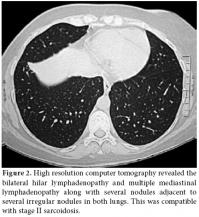

The laboratory testing results were as follows: rheumatoid factor (RF), 11 U/ml (0-20); erythrocyte sedimentation rate (ESR), 67 mm/h (0-20); C-reactive protein (CRP), 85.43 mg/dl (0-5); and the total blood count, urea, creatinine, and electrolyte values were normal. The hepatitis, antinuclear antibody (ANA) along with the Salmonella and Brucella titers were all negative. The purified protein derivative (PPD) skin and pathergy tests were also negative. No findings were detected on the throat culture or in the direct fecal and parasite examinations. HLA-B27 was negative. A chest X-ray showed the hilar plenitude (figure 1). High resolution computed tomography (HRCT) revealed the bilateral hilar lymphadenopathy (LAP) and multiple mediastinal LAP along with several nodules adjacent to several irregular nodules (the largest was 2.5x1.5 cm) in both lungs, which was compatible with stage II sarcoidosis (figure 2). Using a gallium-67 whole body screening method, an activity enhancement in both the hilar and mediastinal regions was consistent with lymph node involvement. The diagnosis of sarcoidosis was confirmed by a bronchoscopic biopsy. A pelvis radiograph and sacroiliac magnetic resonance imaging (MRI) were performed, and the results were normal. The patient was diagnosed as having Löfgren's syndrome, which is a clinical subtype of acute sarcoidosis involving acute arthritis, LAP, and EN. Steroid treatment was administered, and recovery was observed on the arthritis of the right ankle and EN after two weeks. On follow-up, the clinical and laboratory findings (ESR, 35 mm/h; CRP, 7.89 mg/dl) had improved dramatically. During the clinic management of the patient at three months, the patient complained about hip pain, so a radiograph of the sacroiliac joint was performed again. Sclerosis was shown in the inferior regions of both sacroiliac joints on the sacroiliac X-ray (figure 3), and right sacroiliitis was found on the MRI of the sacroiliac joints (figure 4). The complaints of the patient were address by administering nonsteroidal antiinflammatory drugs (NSAIDs), and the patient continued to be followed up.